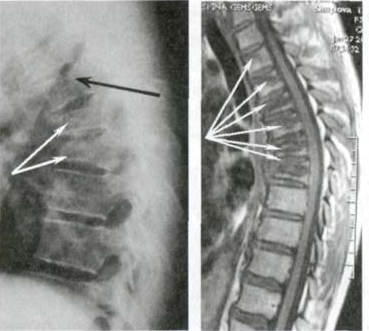

— Apakah Anda benar-benar berpikir bahwa pijat atau analgesik dapat mencegah kerusakan sendi dan tulang rawan? Itu adalah kesalahpahaman besar. Obat-obatan dari apotek tidak dapat meregenerasi jaringan, sementara bahan kimia yang terkandung di dalamnya justru merusak hati dan ginjal seiring waktu. Tubuh tidak dapat selamanya menanggung beban racun ini, dan alih-alih menyelesaikan masalah, Anda justru meracuni diri sendiri! Hal ini terutama berlaku untuk tulang belakang. Semua sendi mengalami keausan, tetapi pada tulang belakang, kurangnya ujung saraf dapat menyembunyikan perubahan yang berbahaya. Kompresi saraf skiatik akibat hernia adalah proses yang menyakitkan, awalnya menyebabkan nyeri ringan di punggung bawah, lalu menjalar ke kaki, menyebabkan kesemutan, mati rasa, dan akhirnya hilangnya fungsi kaki sepenuhnya. Kerusakan yang terus berkembang akan menyebabkan kelumpuhan pada bagian bawah tubuh, dan mengembalikan kendali atasnya menjadi hampir tidak mungkin. Lihat gambar ini. Ini adalah kondisi tulang belakang seseorang yang baru berusia 44 tahun, tetapi tampak seperti lansia. Dulu, kerusakan seperti ini hanya terjadi setelah usia 60 tahun, tetapi sekarang hal ini menjadi umum bagi mereka yang baru saja melewati usia 40 tahun. Kerusakan ini akan terus berkembang seiring bertambahnya usia, dan mengabaikannya berarti menempatkan diri dalam risiko kelumpuhan total!

Hernia cakram tulang belakang, kompresi saraf, kehilangan sensasi, dan kelumpuhan parsial pada kaki.